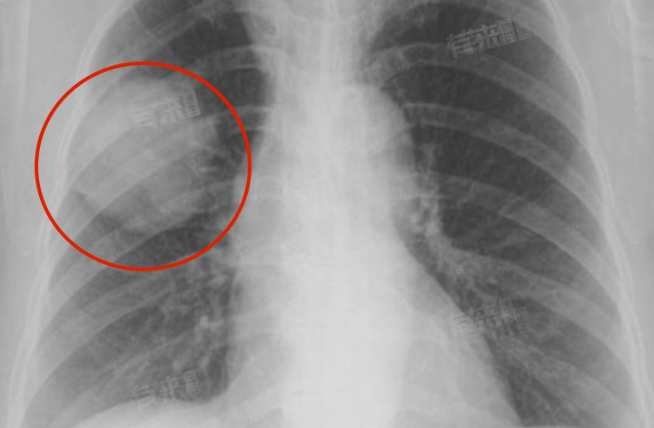

右肺中叶外段实性结节指的是在胸片或肺部CT等影像检查中,发现位于右肺中叶外段的圆形或类圆形的高密度阴影,实质性特征表现为结节的密度相对较高,不能透过结节看到肺纹理的结构。这种结节可能由多种原因引起,包括但不限于感染、炎症、肿瘤等。

- 肿瘤:虽然相对较少见,但实性结节也有可能是肺癌的早期表现,恶性结节通常边缘不光滑,有毛刺征,且可能逐渐增大。

- 进一步检查:如果结节较大、边缘不光滑或有其他恶性征象,需要进一步完善增强CT、肿瘤系列、支气管镜、穿刺活检等相关检查明确诊断。